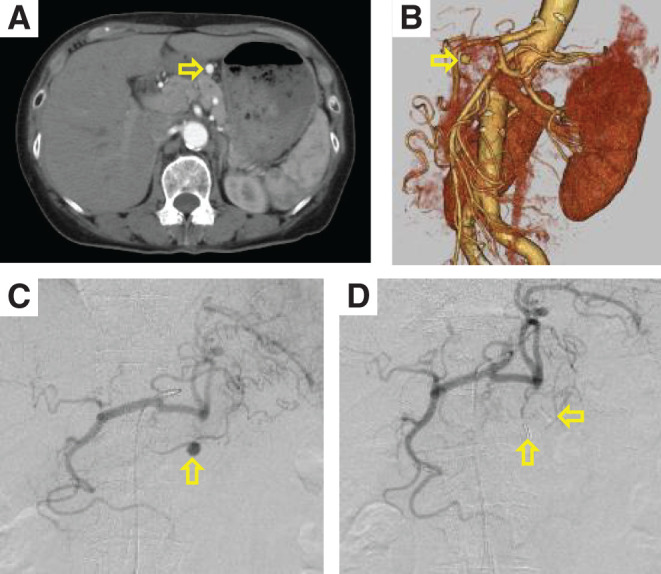

我们报告一例68岁的女性患者有一个8毫米的右胃动脉瘤。血管内治疗的尝试失败,因此患者接受腹腔镜手术切除未破裂的右胃动脉瘤。术后过程顺利,患者目前作为门诊病人接受观察。虽然血管内治疗是治疗未破裂右胃动脉瘤的首选方法,但腹腔镜手术具有侵入性小、解剖可及性和组织病理学检查能力等优点,使其在血管内治疗困难时成为有效的治疗选择。

We report a case of a 68-year-old female patient with an 8-mm right gastric artery aneurysm. The attempt at endovascular treatment was unsuccessful and therefore the patient underwent laparoscopic surgery for the resection of the unruptured right gastric artery aneurysm. The postoperative course was uneventful, and the patient is currently under observation as an outpatient. Although endovascular treatment is the first choice for treatment of unruptured right gastric aneurysms, laparoscopic surgery offers advantages such as less invasiveness, anatomical accessibility, and the ability to perform histopathological examination, making it an effective treatment option when endovascular treatment is difficult.